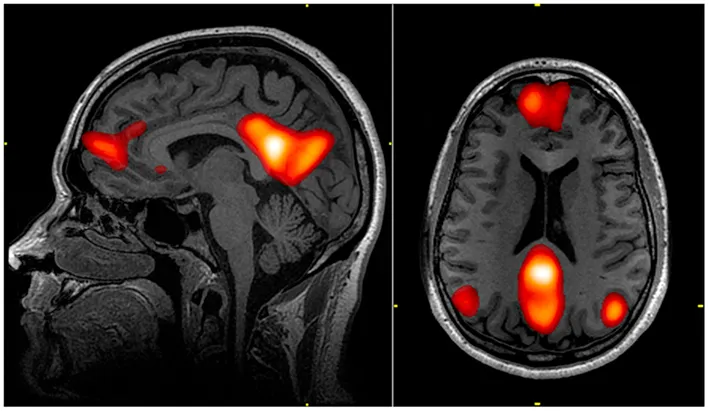

The default mode network — the brain’s self-referential circuit. When you think about yourself, this network activates. The observer, observing itself, using itself. Source: Wikimedia Commons, public domain (WRNMMC).

The default mode network — the brain’s self-referential circuit. When you think about yourself, this network activates. The observer, observing itself, using itself. Source: Wikimedia Commons, public domain (WRNMMC).